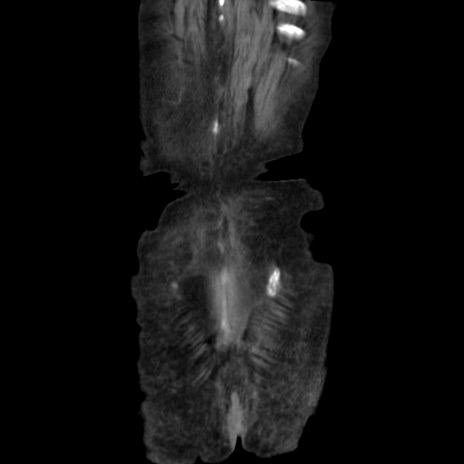

矢状断像